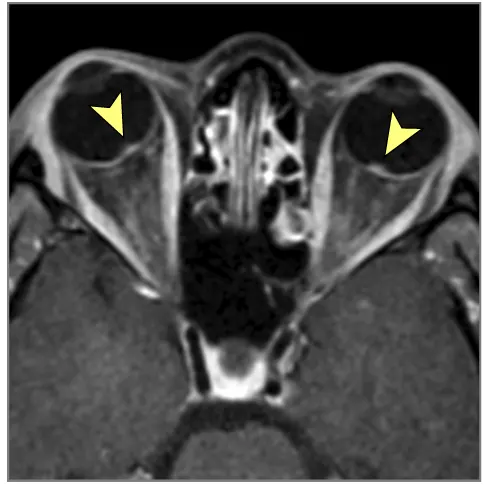

მრტ მიგნებები, რომლებიც მიუთითებს ინტრაკრანიალურ ჰიპერტენზიაზე (ხშირად ჩანს IIH-ში, მაგრამ შეიძლება მოხდეს ქრონიკული აწეული ICP-ის სხვა მიზეზებით) [9]:

- თავის ტვინის მრტ: სასურველი მოდალობა დეტალური ანატომიური შეფასებისთვის. შეუძლია აჩვენოს პარკუჭების გადიდება (ჰიდროცეფალია), გამოავლინოს ობსტრუქციული დაზიანებები (სიმსივნეები, კისტები, წყალსადენის სტენოზი), აჩვენოს მომატებული ICP-ის გართულებები (თიაქარი), აღმოაჩინოს კომუნიკაციური ჰიდროცეფალიის მიზეზები (მაგ., წინა სისხლჩაქცევის/ინფექციის ნიშნები), გამოავლინოს IIH-ის მიმანიშნებელი ნიშნები (ცარიელი კეხი, მხედველობის ნერვის გარსის გაფართოება, უკანა თვალის კაკლის გაბრტყელება, ვენური სინუსის სტენოზი MRV-ზე), ან აჩვენოს ცერებრალური შეშუპების გამომწვევი ძირითადი პათოლოგია (ინსულტი, სიმსივნე, ანთება) (7). სპეციფიკურ მიმდევრობებს (მაგ., CISS/FIESTA) შეუძლიათ შეაფასონ ლიკვორის ნაკადის დინამიკა.

| იდიოპათიური ინტრაკრანიალური ჰიპერტენზია (IIH) | თავის ტკივილი (ხშირად ყოველდღიური, პულსირებადი), პაპილედემა (ჩვეულებრივ ორმხრივი), ვიზუალური დარღვევები (გარდამავალი დაბნელება, ველის დაკარგვა), პულსირებადი ტინიტუსი, +/- CN VI პარეზი. ცნობიერების ნორმალური დონე. ტიპიურად ახალგაზრდა, ჭარბწონიანი ქალები. ნევროლოგიური გამოკვლევა სხვა მხრივ ნორმალურია (გარდა პაპილედემის/CN VI პარეზისა). | ნორმალური მრტ/კტ ტვინის სტრუქტურა (არ არის მასა/ჰიდროცეფალია). მრტ/MRV შეიძლება აჩვენოს მეორადი ნიშნები (ცარიელი კეხი, მხედველობის ნერვის გარსის გაფართოება, უკანა თვალის კაკლის გაბრტყელება, ვენური სინუსის სტენოზი). LP ადასტურებს მომატებულ გახსნის წნევას (>25 სმ წყ.სვ) ნორმალური ლიკვორის შემადგენლობით. |